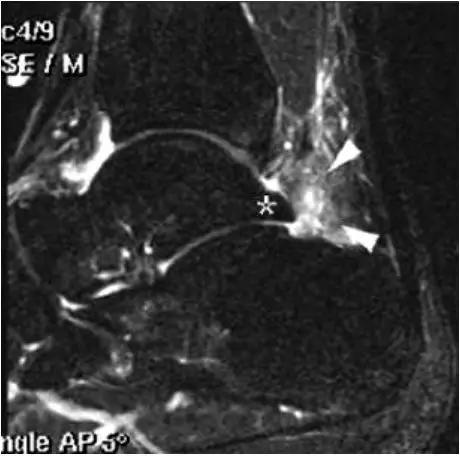

- MRI 检查示距后三角骨及周围软组织有水肿信号,距后三角骨和距骨之间正常的低信号纤维连接中断,出现液性信号。

3、MR表现:

- 三角籽骨或距骨后三角结构模糊和变形,T1WI信号降低, T2WI信号升高,

- 周围脂肪水肿,

- 踇趾长屈肌腱信号升高,见鞘膜积液,

- 胫骨后下跟骨上缘骨结构形态变化和信号异常,

- 三角籽骨和距骨退行性囊变。

三角籽骨综合征

三角籽骨综合征并跟腱滑囊积液